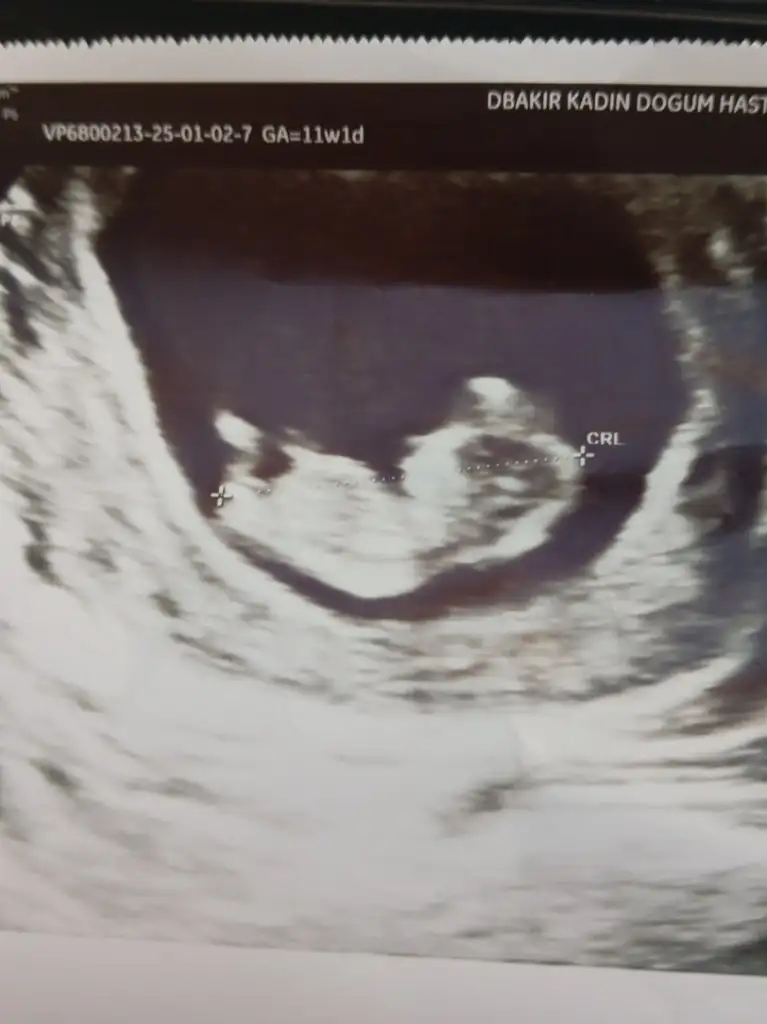

Bende de ilk ultrasondaki gibi erkek dediler 3 doktordaMerhabalar 16. Haftalık hamileyim doktor bir erkek dedi ama sonra kordon olabilir dedi bugun baska doktorda randevum vardi cinsiyet icin oda aynı seyi soyledi net degil kordon olabilir dedi ama bacak arasına bakıldıgında bence net gibi sizin fikirlerinizi merak ediyorum. Yorumlarınızı lutfen paylasir mısınız?

Peki belli oldu mu cinsiyetiniz ? Bacak arasında birsey var ama bizimkinde bence o kordon degildir gibime geliyorBende de ilk ultrasondaki gibi erkek dediler 3 doktorda

16. Haftada erkek diyorlarsa bence kordon değildir erkekler daha çabuk belli oluyorPeki belli oldu mu cinsiyetiniz ? Bacak arasında birsey var ama bizimkinde bence o kordon degildir gibime geliyor

İki oğlum var birine hamileyim henüz. İkinci gebeliğimde cinsiyeti bizzat kendim gördüm ve Dr şaşırdı ultrasondaki doktor da şaşırdı sağlıkçı değilim deyince. Yani bence erkek o testise benziyor ortadaki ama pipi görmedikleri için net konuşmamışlardır.